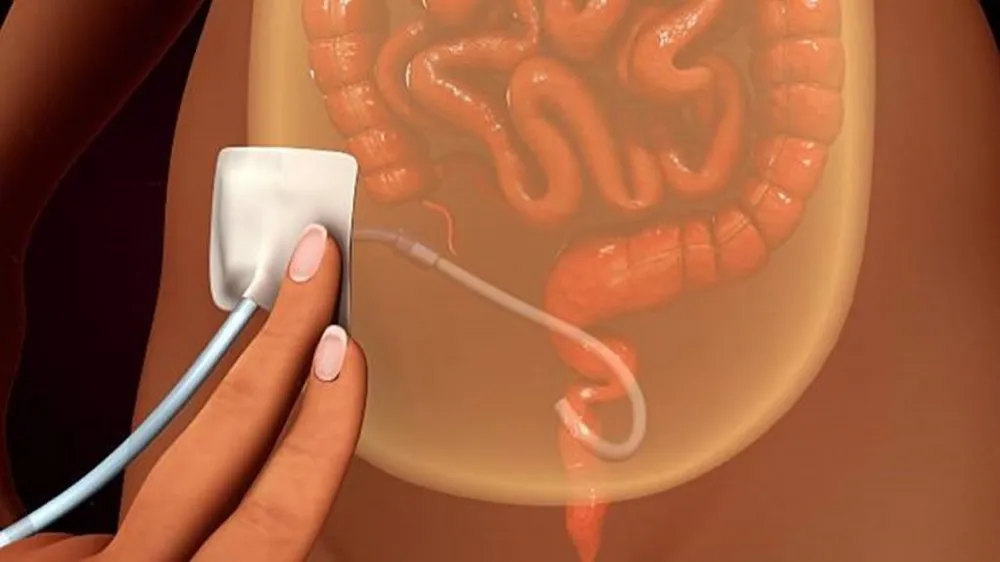

A DRPAD não é contraindicação à DP — e, na prática, muitos pacientes têm resultados comparáveis à hemodiálise. O “porém” está na mecânica: rins/hepatomegalia podem reduzir tolerância a volumes, aumentar risco de hérnias e extravasamentos, e piorar desconforto respiratório. Com técnica adequada (cateter presternal ou lateral, volumes menores, cicladora noturna e decúbito supino), a maioria das barreiras é contornável. Neste post, revisamos quando a DP é ótima, quando exigir cautela e como ajustar a prescrição para segurança e qualidade de vida.